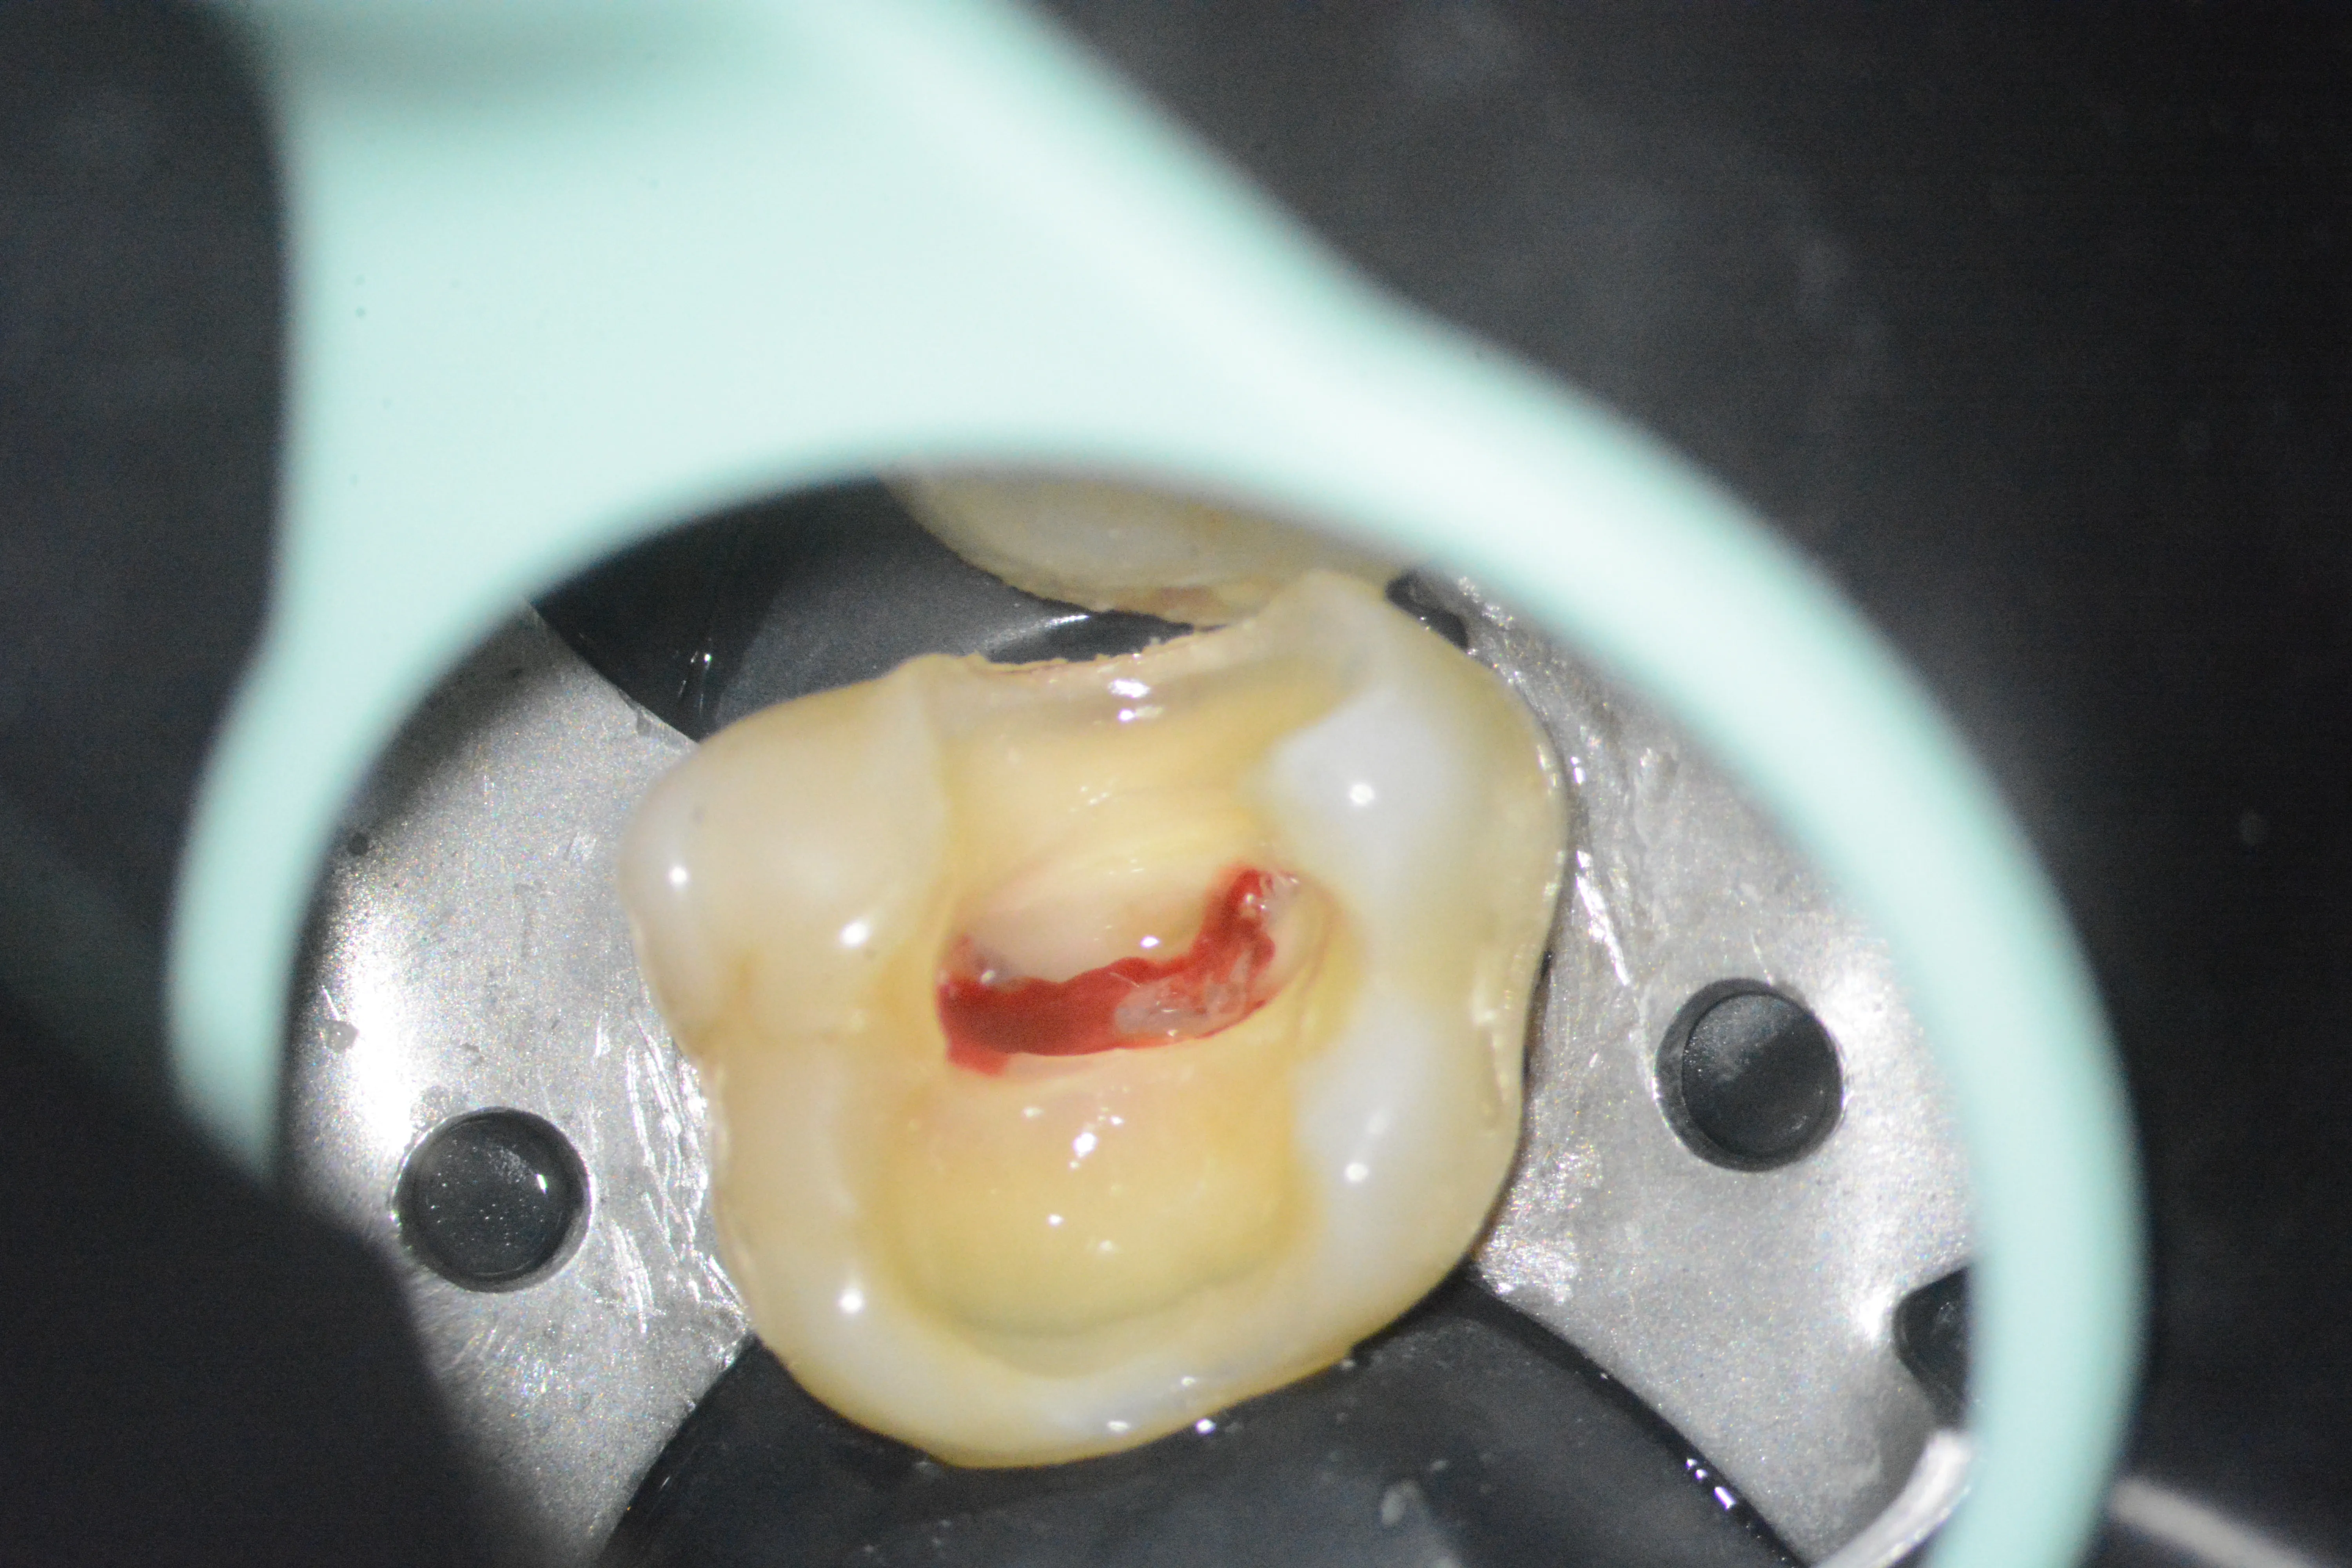

3 – Aspectul pulpei coronare